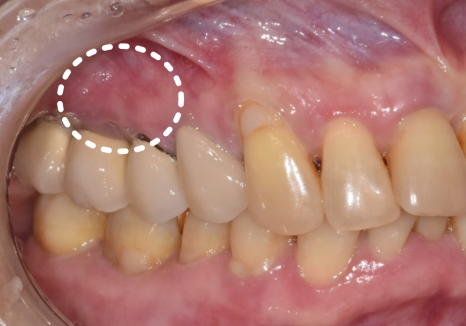

불편함을 호소하시는 환자분의 입안을 보니,

상황은 생각보다 좋지 않았는데요..

잇몸은 붉게 부어올라 있었고,

살짝만 눌러도 노란 고름이 배어 나오는 상태...

230216